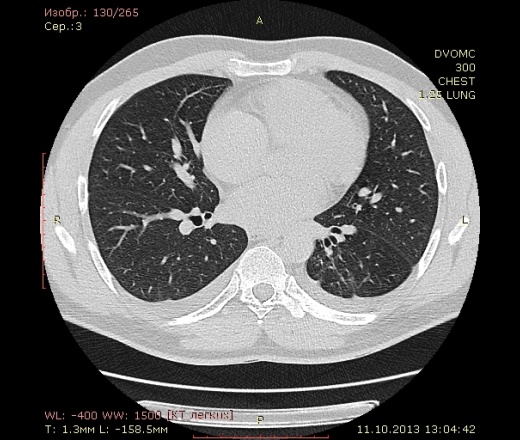

Пациент 35 лет. На УЗИ нашли житкость слева в плевральной полости, отправили на КТ - жидкость с обеих сторон. Из разговора с больным выяснилось, что около 1,5 месяцев назад была высокая тенпература, кашель - никуда не обращался и не лечился. На момент исследования ни на что не жалуется.

Похоже слева в S10? на поствоспалительные изменения? или на что похуже? И если на стороне поражения можно понять окуда жидкость, то справа - можно расценивать как реакция плевры на воспаление слева?

Локальный фиброз субсегмента S10 слева с бронхоэктазами. Двусторонний малый гидроторакс (толщина слоя жидкости до 1 см≈объём до 50 мл). Интересная субкапсульная ерундовина в S6 печени, наверное киста.